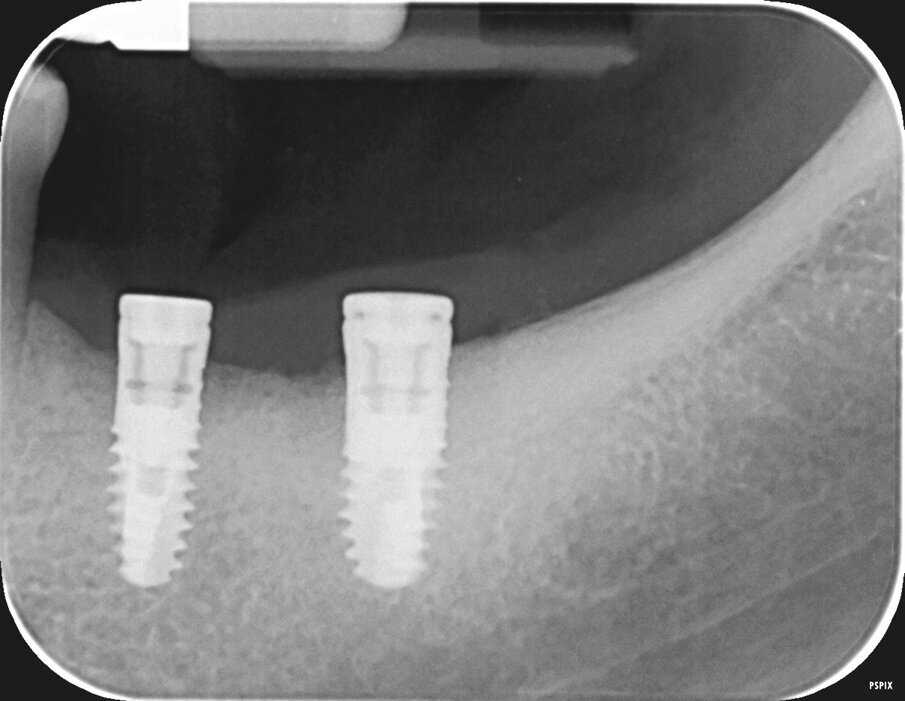

Il caso in esame riguarda una paziente di 53 anni, fumatrice, che si presentava all’osservazione per il consueto controllo periodico lamentando sanguinamento e dolore gengivale durante le manovre di igiene orale a livello di due impianti situati in posizione 4.6 e 4.7. A seguito dell’esecuzione di una CBCT per altri motivi si è potuto evidenziare un marcato riassorbimento osseo perimplantare (Fig. 1). Come si può osservare durante la chirurgia (Fig. 3) l’esposizione della superficie implantare è superiore al 50%. In entrambe le fixture con un maggior coinvolgimento in posizione 4.6. È stata inoltre riscontrata una sofferenza della mucosa attorno ai monconi delle due fixture.

L’innesto è stato protetto con due membrane, opportunamente sagomate e forate per adattarsi attorno a ciascun impianto (Fig. 7). L’operazione è terminata con la sutura dei lembi gengivali tramite filo in poliammide non riassorbibile (Monomyd 4-0, Butterfly, Cavenago) e il posizionamento di due viti di guarigione (Fig. 8). La sutura è stata rimossa a 12 giorni dall’atto chirurgico. Una radiografia di controllo al termine dell’intervento ha confermato l’effettivo ripristino dei volumi ossei perimplantari (Fig. 9). Durante il periodo di guarigione e ai successivi controlli, non si sono osservati segni di sofferenza gengivale (Fig. 10). La paziente non ha lamentato alcuna sintomatologia spontanea o evocata. Al controllo a 3 mesi, l’esame radiografico mostrava il mantenimento dei profili ossei perimplantari (Fig. 11). Sono state quindi rimosse le viti di guarigione e riposizionate le corone.

Fig. 1 - CBCT in sezione laterale. I coni di riassorbimento coinvolgono un’ampia porzione della superficie implantare.

Fig. 9- Radiografia endorale di controllo al termine dell’intervento.

Fig. 11 - Controllo radiografico a 3 mesi, i livelli perimplantari sono mantenuti.